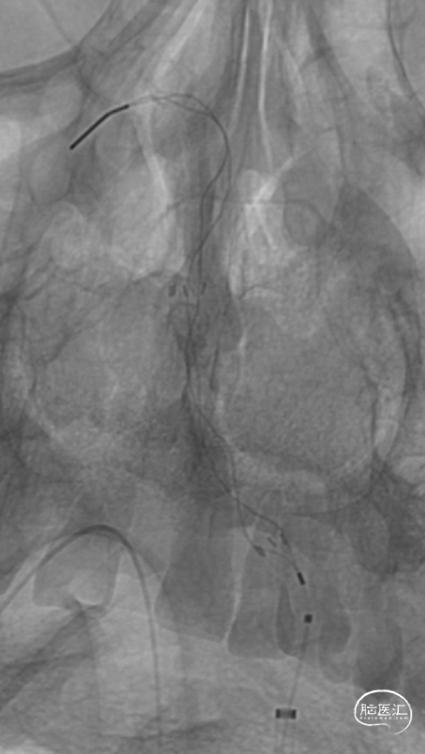

8F股动脉鞘

0.035in泥鳅导丝

5F VTK

6F 90cm 长鞘

5F 115cm Tethys®中间导引导管

Headway 17微导管

200cm、300cm 0.014in ASAHI 微导丝

2.0mm*15mm Sprinter球囊

加奇4.0mm*30mm Syphonet®取栓支架

急诊DSA:Ⅱ型弓,基底动脉AICA以远未见显影。

加奇Tethys®中间导引导管到位,明确既往支架位置。但中间导管通过困难。